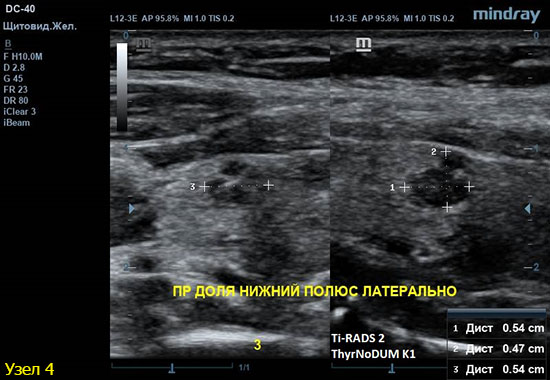

4) Узел правой доли, не прорастает капсулу щитовидной железы (0 баллов), больше широкий чем высокий (0 баллов), не имеет кальцинатов (0 баллов), с ровным четким контуром (0 баллов), изоэхогенный (1 балл), смешанной структуры (кистозно солидный) (1 балл). Количество баллов 2, ACRTi-RADS2, ThyrNoDUMК1. Пункция не показана в связи с низким риском.